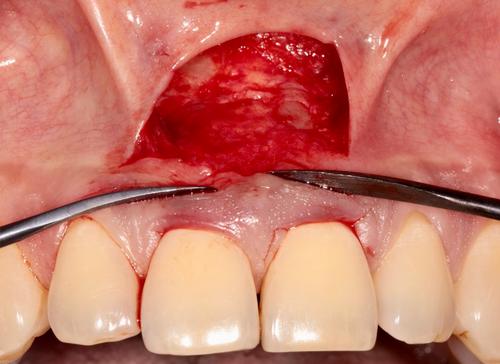

A patient presented to the periodontics clinic with concerns regarding gingival recession. A modification to the semilunar technique was employed to address the recession, whereas double sling sutures were utilized to maintain the coronal repositioning of the flap.

Maxillary central incisors initially presented with 2–3 mm of facial recession and root coverage was achieved by use of a modified surgical semilunar approach. No rebound noted over a 6-month period, newly established gingival margin deemed clinically stable.